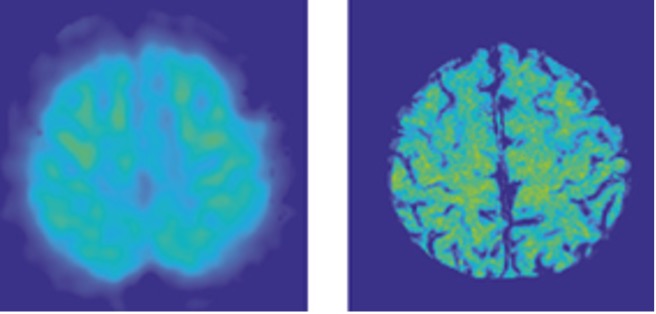

Prior OEF mapping requires use of various oxygen-related gas manipulation in positron emission tomography (PET, left) or MRI, which are difficult to perform. QSM based OEF (right) enables manipulation-free mapping in routine MRI.

Cerebral oxygen extraction fraction (OEF): Comparison of challenge-free gradient echo QSM+qBOLD (QQ) with 15 O PET in healthy adults. Cho et al. J Cereb Blood Flow Metab. 2021 Jul;41(7):1658-1668. doi: 10.1177/0271678X20973951.